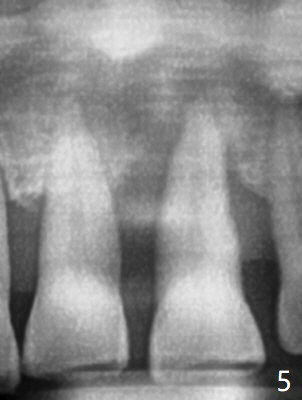

A 67-year-old man requests extraction of the loose tooth #9 (Fig.1). After extraction, the labial plate is found to be missing. With incision, allograft is kept in place with a 12x24 mm anterior narrow Cytoplast and 4-0 Chromic gut suture (Fig.2). Periodontal dressing dislodges in 2 days. The wound dehisces transversely 5 days postop (Fig.3 arrows), whereas the wound was open buccopalatal when the sutures were placed. Probably due to extensive dissection, the erythematous mucosa is large (Fig.4), although asymptomatic. When X-ray shows V-shaped bony defect (Fig.1 (PA), 5 (Pan), 6 (CT)), do not dissect the overlying thin buccal gingiva, which is most likely to dehisce. In fact immediate implant with guide appears to be more conservative, since there is no pressure against the buccal gingiva (Fig.7,8). To be more ideally, the implant could be placed more coronally, longer (13 mm instead of 11.5, Fig.9,10) and narrower (3.5 mm instead of 4.0 mm, Fig.11 (red circles: bone graft)).